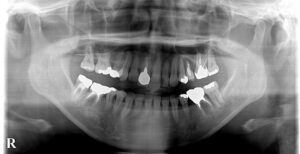

🔶初診時パノラマ🔶

しかし皆様から見て右上は

歯周病で矯正後に

歯がグラグラになるかも

そんな時は

インプラントを行う事で

了解を得て開始